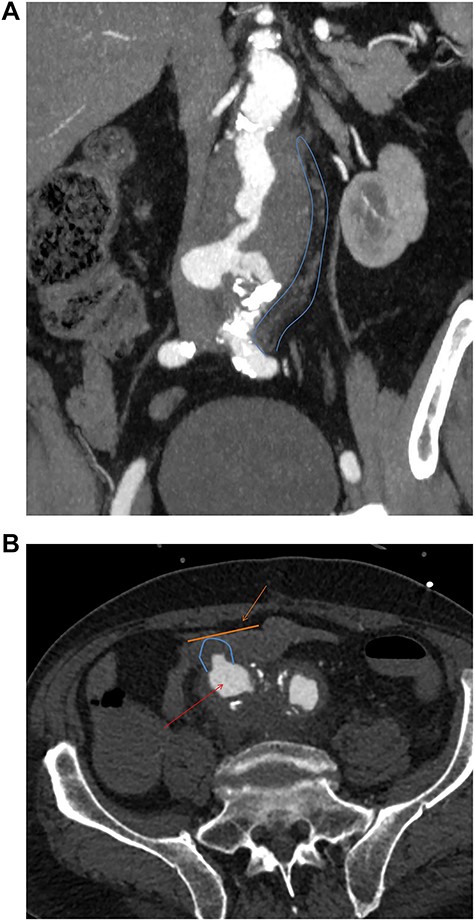

The second case is a 75-year-old gentleman with a background of ulcerative colitis who underwent an elective open tube graft repair for an 8 cm inflammatory aneurysm. In retrospect, inflammatory features are seen to extend distally to the iliac bifurcation on initial imaging (Fig. 2a). Thus, the patient may have benefited from the management of this at the initial surgery.

(a) Preoperative coronal thick slice of a CT with IV contrast in the arterial phase shows aneurysmal aorta with normal calibre common iliac arteries; however, inflammatory change around the aortic aneurysm is seen extending into the proximal iliac bifurcation (blue outline); (b) axial slice of a CT with IV contrast in the arterial phase shows aneurysmal common iliac arteries (red arrow), a clear saccular bulge (blue outline) into an adhered loop of small bowel (orange outline and arrow); the site of the fistulation.

Fourteen months later, he presented to the emergency department with melaena and haemoglobin of 62 g/l. Following resuscitation an OGD was normal and CT angiography was unable to determine any definitive active bleed but suggested a possible AEF given the close proximity of the third part of duodenum to the aortic graft. Twenty-four hours later, the patient collapsed with a large amount of melaena and frank rectal bleeding in hemorrhagic shock. A new CT scan showed an AEF between distal right common iliac artery and ileum (Fig. 2b) not associated with the suture line of the previous open repair. Of note, this was found to be present on initial emergency imaging when reviewed by a specialist vascular radiologist.